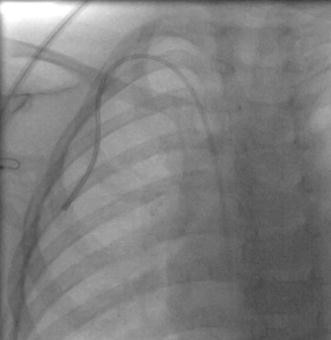

Fig. 2

figure 2

Fluoroscopic image demonstrating the tip of the PICC used as a TCVC at the superior vena cava-right atrium junction. We typically aim for catheter position in the right atrium